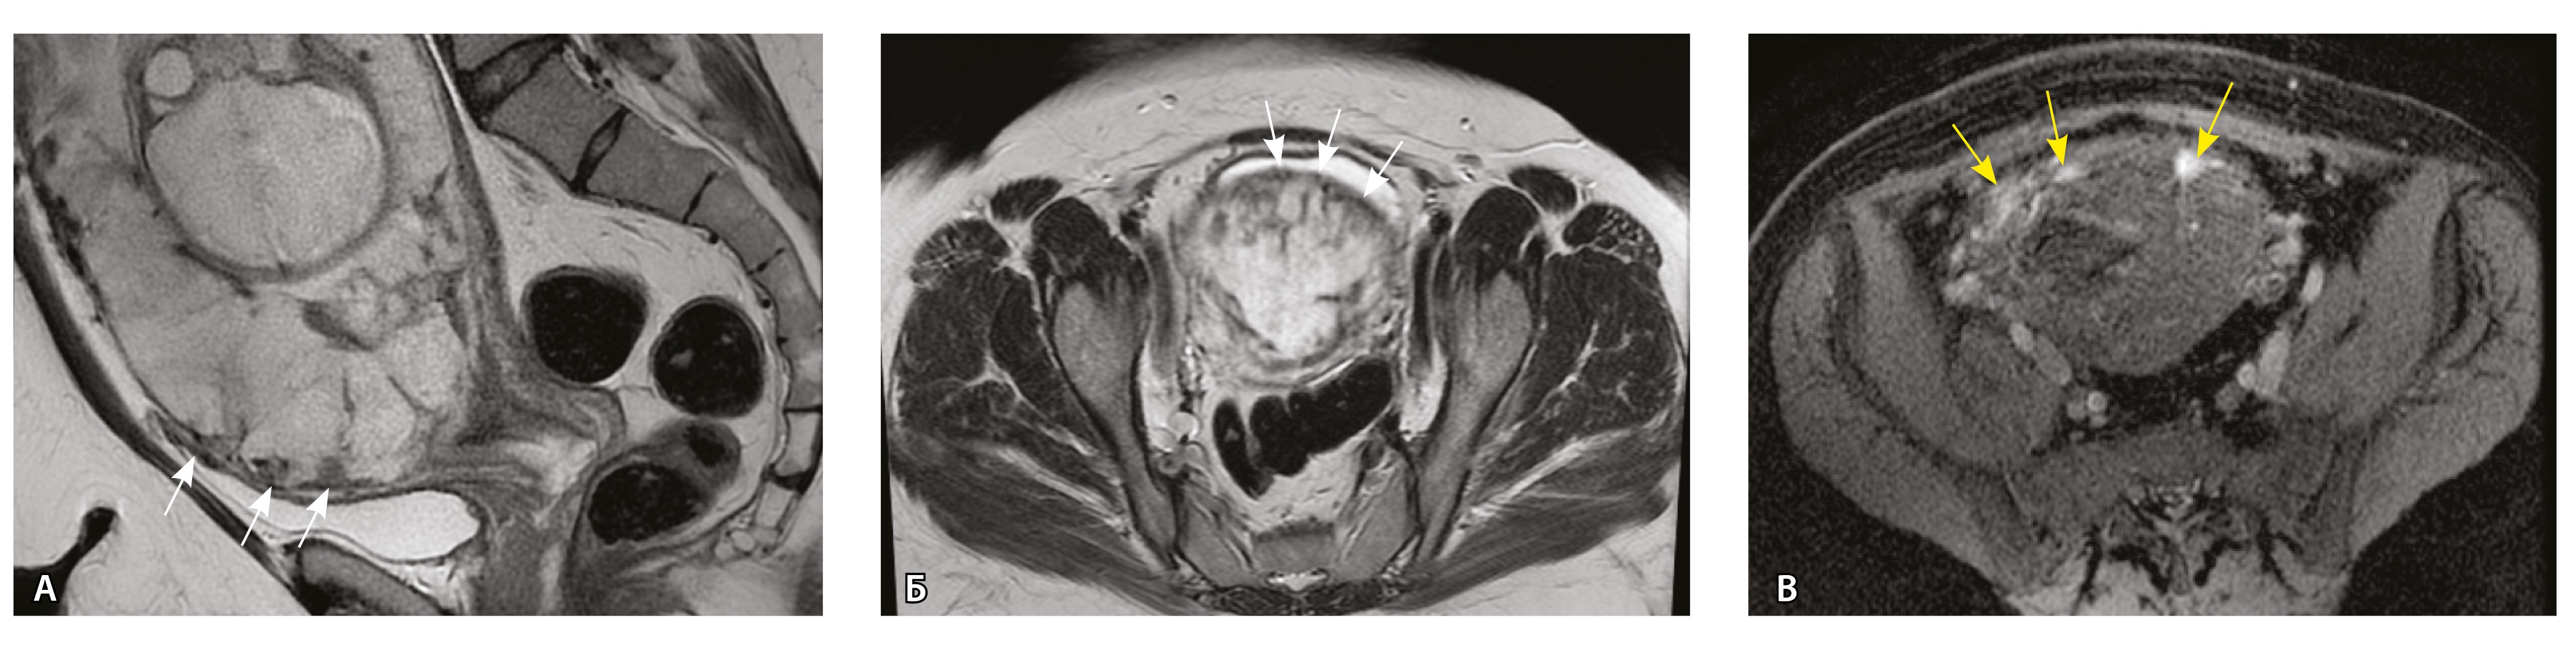

Сосуды 1-го типа. Единичные сосуды в миометрии и пограничных отделах в маточно-плацентарной области (рис. 2).

Рис. 2. Беременность 32 недели, центральное предлежание плаценты без признаков приращения. На магнитно-резонансных томограммах в режиме Т2-взвешенного изображения (Т2ВИ) в сагиттальной плоскости (А) и Т2ВИ с подавлением сигнала от жировой ткани во фронтальной плоскости (Б) видны мелкие ретроплацентарные сосуды, расположенные на границе плаценты и рубца на матке от кесарева сечения (белая стрелка) либо плаценты и миометрия (желтые стрелки; плацентарная площадка указана белой пунктирной линией). Фото микропрепарата: В – визуализируются мелкие артерии и вены в составе серозной оболочки, стрелкой указан слой мезотелия (окраска азокармином по Маллори; × 50); Г – маточно-плацентарный сегмент, стрелкой указан сосуд в толще миометрия на границе с плацентой (окрашивание гематоксилином и эозином; × 50)

В смежных участках строение стенки матки было представлено миометрием с разной ориентацией мышечных пучков и тонкими соединительнотканными прослойками. Сосудистая система состояла из синусоидов – тонких полостей в срединном слое миометрия, а также пре- имущественно мелких артерий в составе серозной оболочки. Только единичные из них визуализировались на МРТ, так как данным методом ввиду технических особенностей невозможно визуализировать самые мелкие сосуды и серозную оболочку матки из-за ее малой толщины. Тем не менее это важно для сравнения картины нормы с последующей гиперваскуляризацией при различных степенях PAS.

Сосуды 2-го типа. Единичные сливающиеся сосудистые полости в маточно-плацентарной области, мелкие ретроплацентарные гематомы, участки с белковым содержимым по МР-сигналу в зоне контакта ворсин со стенкой матки (рис. 4).

Рис. 4. Беременность 32 недели, pl. accreta, PAS 1 по FIGO. На магнитно-резонансных томограммах в режиме Т2-взвешенного изображения в сагиттальной (А) и аксиальной (Б) плоскостях видны сосуды на границе маточно-плацентарной области, сливающиеся между собой (белые стрелки), без выраженного дефицита толщины миометрия и рубца от кесарева сечения, без признаков выбухания стенки матки. На Т1-взвешенном изображении в режиме подавления сигнала от жировой ткани в аксиальной плоскости (В) выявляется наличие участков повышенного сигнала (желтые стрелки) на границе маточно-плацентарной области, что соответствует геморрагическому компоненту в подострой/хронической стадии (ретроплацентарные гематомы) либо белковому содержимому (фибриноид)

Непосредственное сравнение МР-картины с операционным материалом подтвердило, что полости с геморрагическим компонентом соответствовали ретрохориальным гематомам различной давности, чаще подострой и хронической стадий, которые состояли из гемолизированных эритроцитов, нитей фибрина сетчатого строения, а также замурованных атрофичных ворсин (рис. 5). Следовательно, констатация на МРТ фиксированных геморрагических полостей в маточно-плацентарной области отражает не гиперваскуляризацию стенки матки, а наличие ретрохориальных гематом в подострой/хронической стадии, что следует учитывать в клинической практике.

Сосуды 3-го типа. Внутриматочная гиперваскуляризация с дефицитом толщины миометрия, преимущественно сосуды срединного слоя, аналог pl. increta PAS 2, гестационная перестройка радиальных артерий (рис. 7).

Рис. 7. Беременность 34 недели, pl. increta, PAS 2 по FIGO. На магнитно-резонансных томограммах в режиме Т2-взвешенного изображения в сагиттальной (A, Б) и фронтальной (В) плоскостях определяется внутриматочная гиперваскуляризация с наличием многочисленных сливающихся сосудов в толще стенки матки, в области плацентарной площадки (белые стрелки); в нижнем маточном сегменте – выраженное истончение стенки матки, рубца от кесарева сечения с формированием маточной грыжи (желтые стрелки)

Тип 1. Единичные мелкие сосуды в миометрии, артерии среднего калибра в проекции серозной оболочки матки (аналог нормы в III триместре беременности).

Тип 2. Многочисленные мелкие сливающиеся сосуды, преимущественно в маточно-плацентарной области (место взаимодействия терминальных ворсин со стенкой матки), возможно обнаружение ретроплацентарных гематом (характерно для pl. accretа, PAS 1 по FIGO).

Тип 3. Внутриматочная гиперваскуляризация с дефицитом толщины миометрия, наличием рубцовой ткани, недостаточная гестационная перестройка радиальных артерий (характерно для pl. increta, PAS 2 по FIGO).